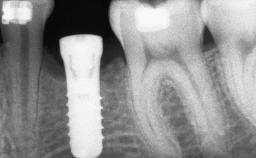

# of Implants 1

Type of Implants Two-Piece

Bone Augmentation Staged|Vertical

Augmentation Materials Autogenous chips|Membrane

Bone Volume Deficient vertically or deficient vertically AND horizontally